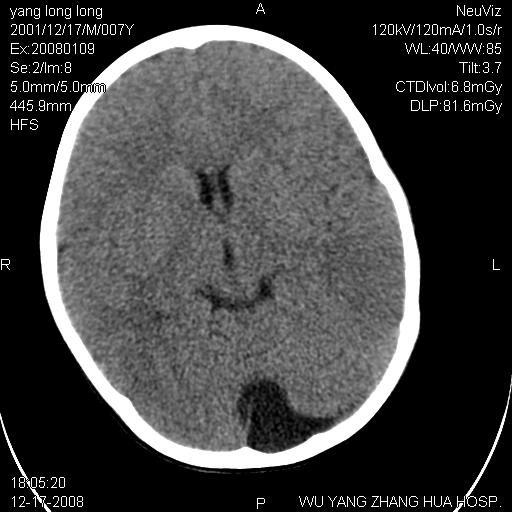

标题: PED1686:M7Y,头外伤,家人及自诉平时无任何不适。 [打印本页]

标题: PED1686:M7Y,头外伤,家人及自诉平时无任何不适。

考虑蛛网膜囊肿,请老师们看看多指导指导。

多考虑大枕大池。本例颅骨歪歪的,灶后枕骨似有膨胀征像(为蛛网膜囊肿征像),但整个左侧枕叶后方枕骨均有向后膨隆,所以暂不考虑蛛网膜囊肿。必要时随访

鉴别巨大枕大池与蛛网膜囊肿之间,倾向前者。